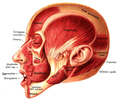

Muscles of the head, face, and neck. (Nasalis labeled at center left.) | |

Position of nasalis muscle (shown in red).